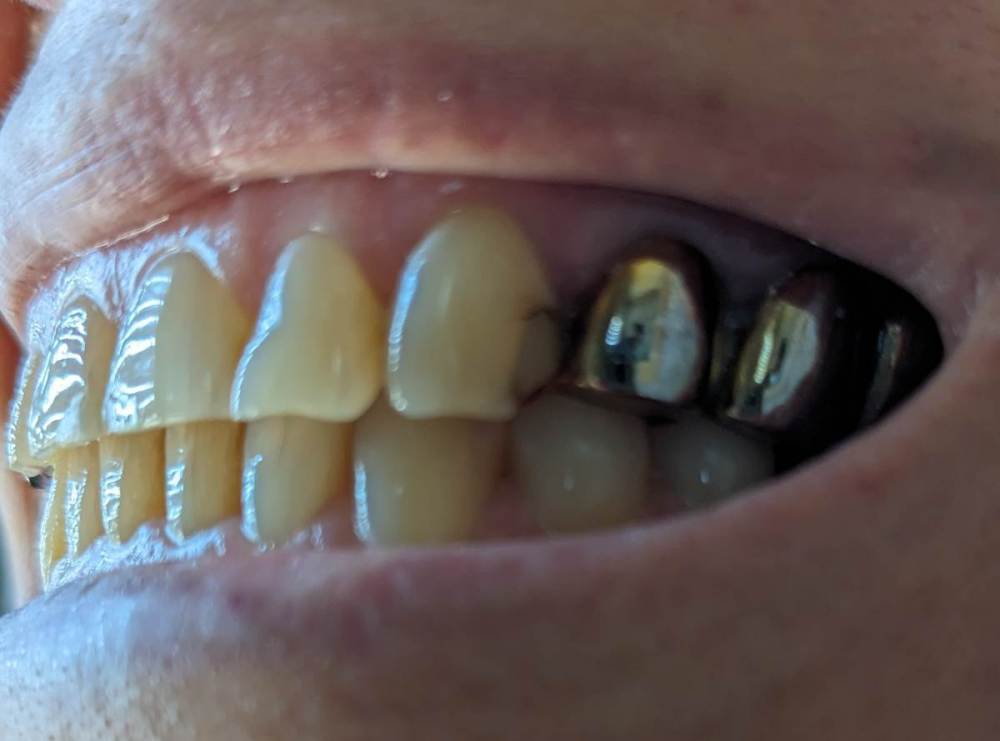

после сильного стресса нарушился прикус. на верхней челюсти боковые зубы сдвинулись вовнутрь, а передние ушли немного вперёд.

в детстве были полностью вырваны 4 и 5 зубы справа, и 6 слева. на боковых зубах справа и слева стоят рандолевые мосты - по четыре жевательных зуба (справа 3, 4, 5, 6 зубы. слева - 4 это отдельная коронка, а 5, 6, 7 - мост). хочу поменять эти мосты на металлокерамические. и есть желание выровнять кривой зуб (2 справа).

врач, который ставит коронки, говорит что новые мосты полностью исправят прикус, но есть сомнения, ведь передние зубы мосты не затронут.